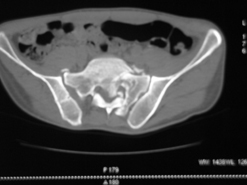

Диагноз : Сочетанная травма. ЗЧМТ. Перелом свода черепа. Ушиб головного мозга.Разрыв лонного и крестцово-подвздошного сочленений с нарушением целостности тазового кольца, с массивной забрюшинной гематомой и пропотеванием в брюшную полость. Перелом 10 ребра справа, осложненный гемопневмотораксом справа, правосторонней пневмонией на фоне ушиба правого легкого. Шок 3-4 ст. Больной поступил в отделение 07.03.2005г. в 16.00 в экстренном порядке через 30 минут после автодорожной травмы.Доставлен КСП. При поступлении состояние больного крайне тяжелое, явления травматического шока, А/Д-80/60 мм.рт. ст. ЧСС-120.В экстренном порядке поднят в операционную, интубирован, совместно с диагностическими мероприятиями лечение шока.При осмотре выявлены перелом 10 ребра справа, разрыв лонного и правого крестцово-подвздошного сочленений. Имеется линейный перелом теменной и височной костей слева с переходом на основание. Диагностическая лапароскопия 07.03.2005г. в 16.30-массивная забрюшинная гематома малого таза.Оставлена контрольная, дренажная трубка.Учитывая кровь в моче произведена цистография - данных за разрыв мочевого пузыря не найдено. Больной переведен в реанимационное отделение.За 08.03.2005г. из брюшной полости выделилось до 1500,0 мл, крови, часть крови реинфузирована. 08.03. в 06.30 наложен торокоцентез справа,удалено 100,0 мл. крови и 200,0 мл. воздуха .. Учитывая продолжающеееся кровотечение в брюшную полость из перелома костей таза, для исключения возможного разрыва внутренних органов 09.03.2005г. произведена Видеолапароскопия., на которой повреждения органов брюшной полости не выявлено.Одновременно произведен шов лонного сочленения проволокой и винтами, с одномоментным наложением стержневого аппарата на кости таза, с целью уменьшения кровотечения из разрывов тазовых сочленений, дренирование гематом. В последующем состояние больного оставалось тяжелым. 10.03.наложена нижняя трахеостома.Далее неоднократно производилась лечебно-диагностическая ФБС.С 10.03 выявлена правосторонняя плевропневмония. КТ головного мозга от 10.03-субарахноидальноекровоизлияние.Срединные структуры не смещены. КТ-контроль от 15.03-открытая моновентрикулярная гидроцефалия4 желудочка. Полисинусит. Постепенно состояние больного медленно прогрессировало к улучшению.С 24.03 переведен на самостоятельное дыхание, а 09.03 переведен в травматологическое отделение.Аппарат стержневой снят из-за перелома стержня (раскрутил больной самостоятельно).После госпитализации в наше отделение проведено дополнительное обследование Рентгекнография, КТ.Хотелось бы услышать Ваше мнение о дальнейшей тактике.-- С уважением, Leonid

Углядел билатеральное повреждение таза. Имеется вертикальная нестабильность со стороны перелома боковой массы крестца, ротационная с контрлатеральной стороны - чрезподвздошный разрыв кп сочленения. Разрыв лона, запирательные отверстия вроде целы.

DS. на сегодняшний день: Вертикальная двусторонняя нестабильная деформация таза, неправильно срастающийся перелом боковой массы крестца слева, срастающийся перелом крыла правой подвздошной кости, застарелый частичный разрыв правого кп сочленения, застарелый разрыв лонного сочленения.